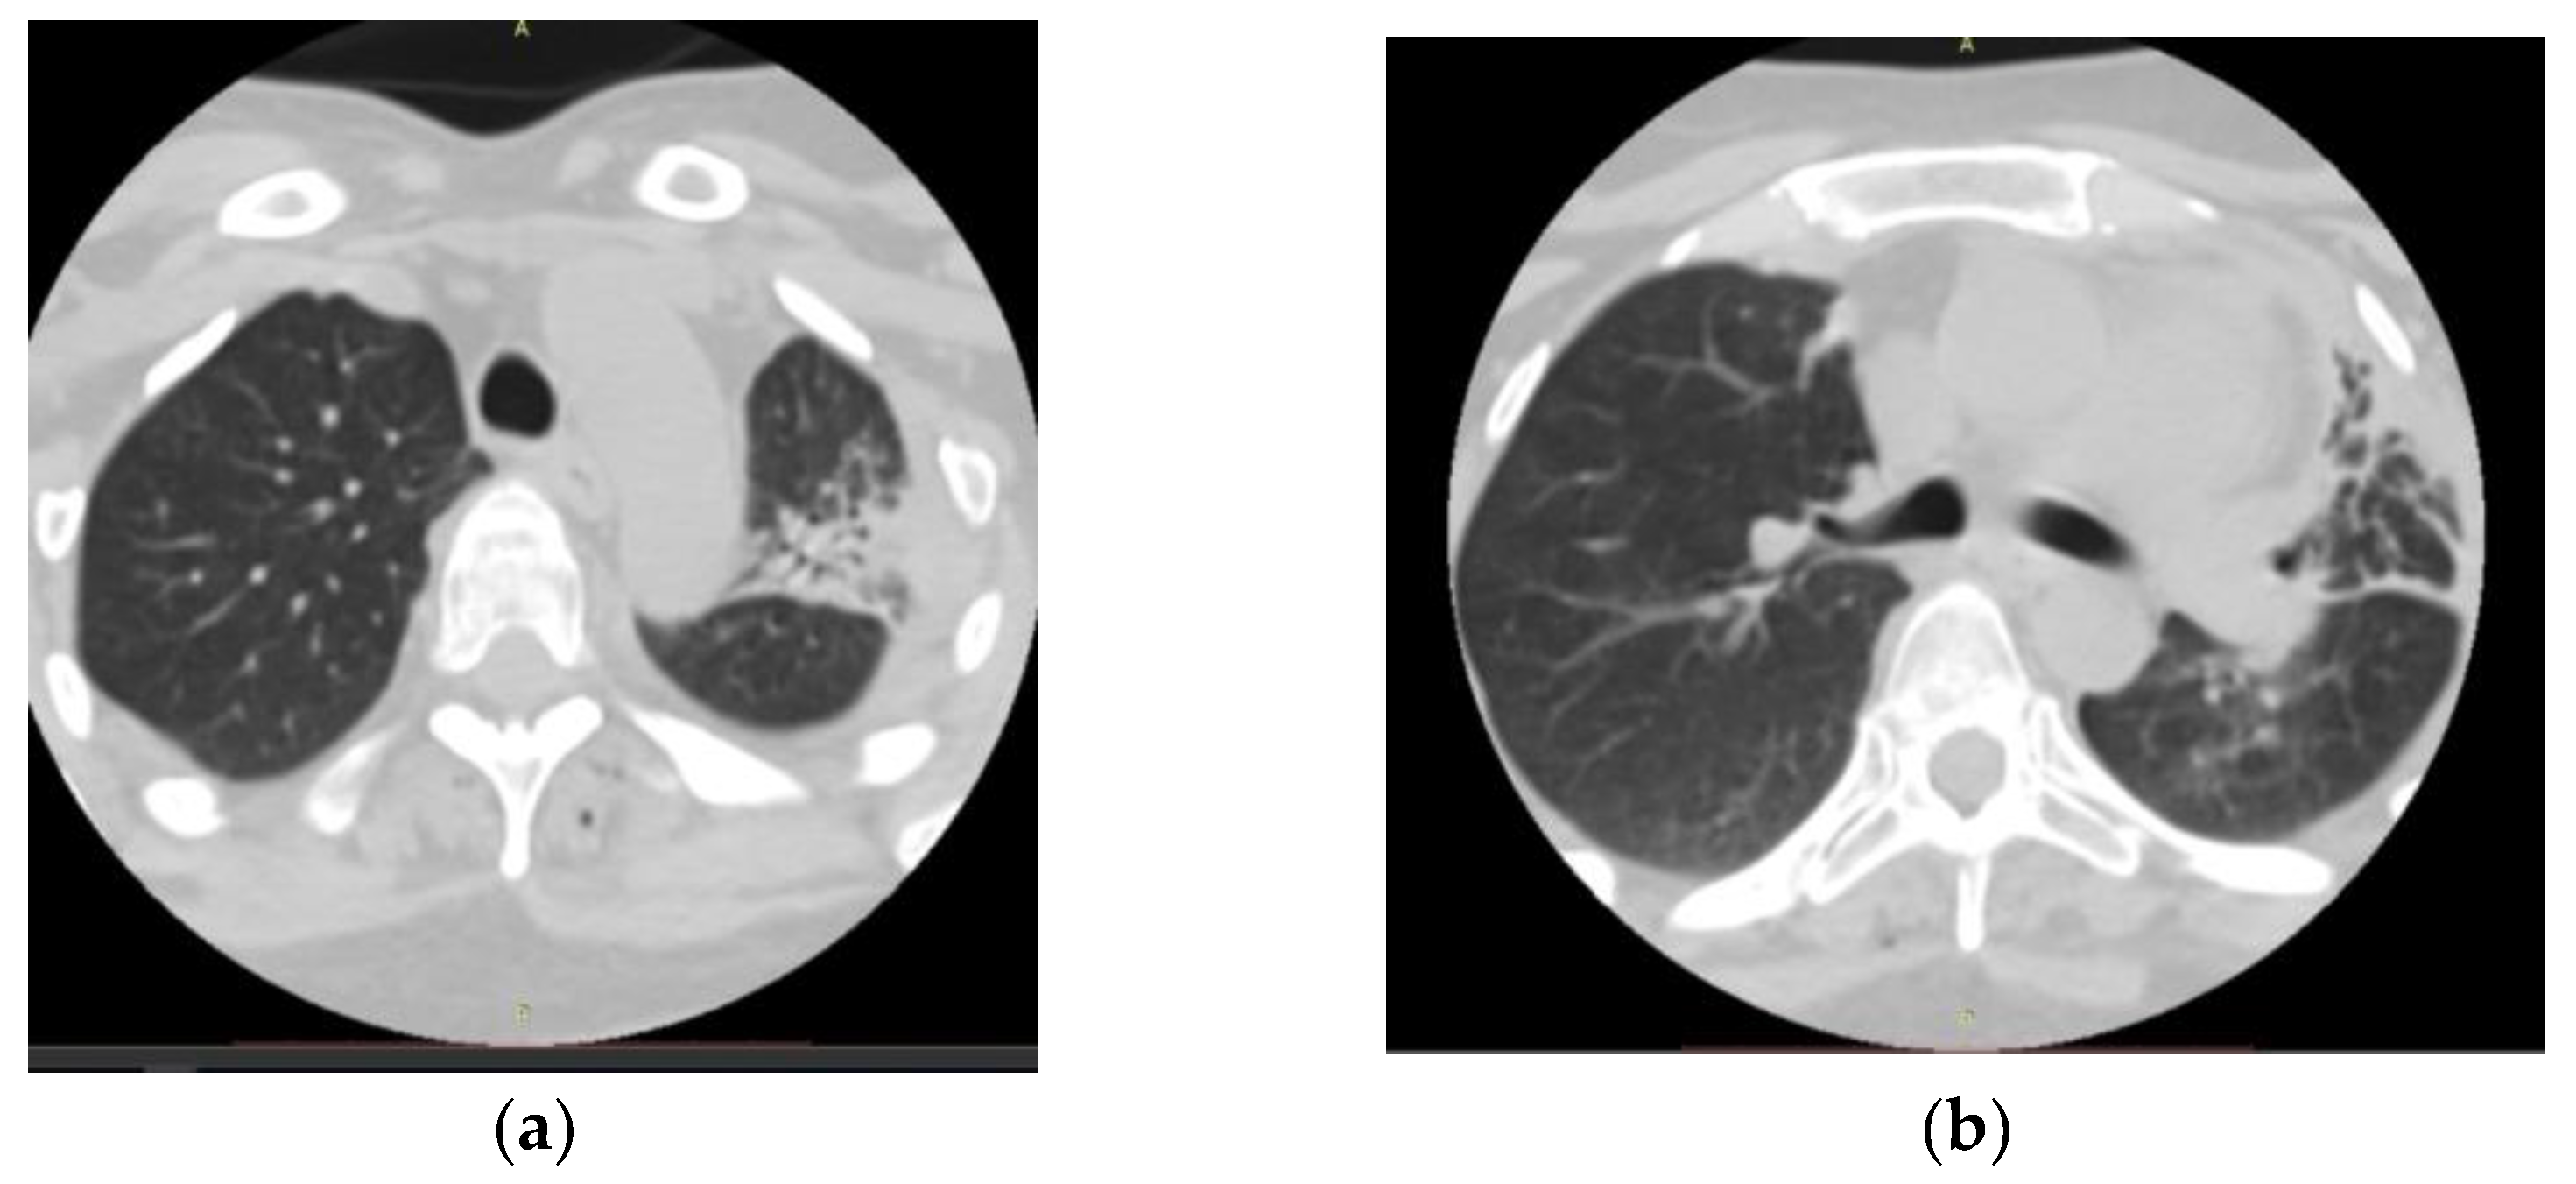

2. Detailed Case Description

- Radiological evidence of chronic pulmonary lesion;

- Mycological demonstration of Aspergillus fumigates hyphae by microscopy from spu-tum, microscopy and culture from bronchial aspirate, and histopathological evi-dence of the presence of Aspergillus fumigates hyphae with dichotomous branching in the spinal cord biopsy;